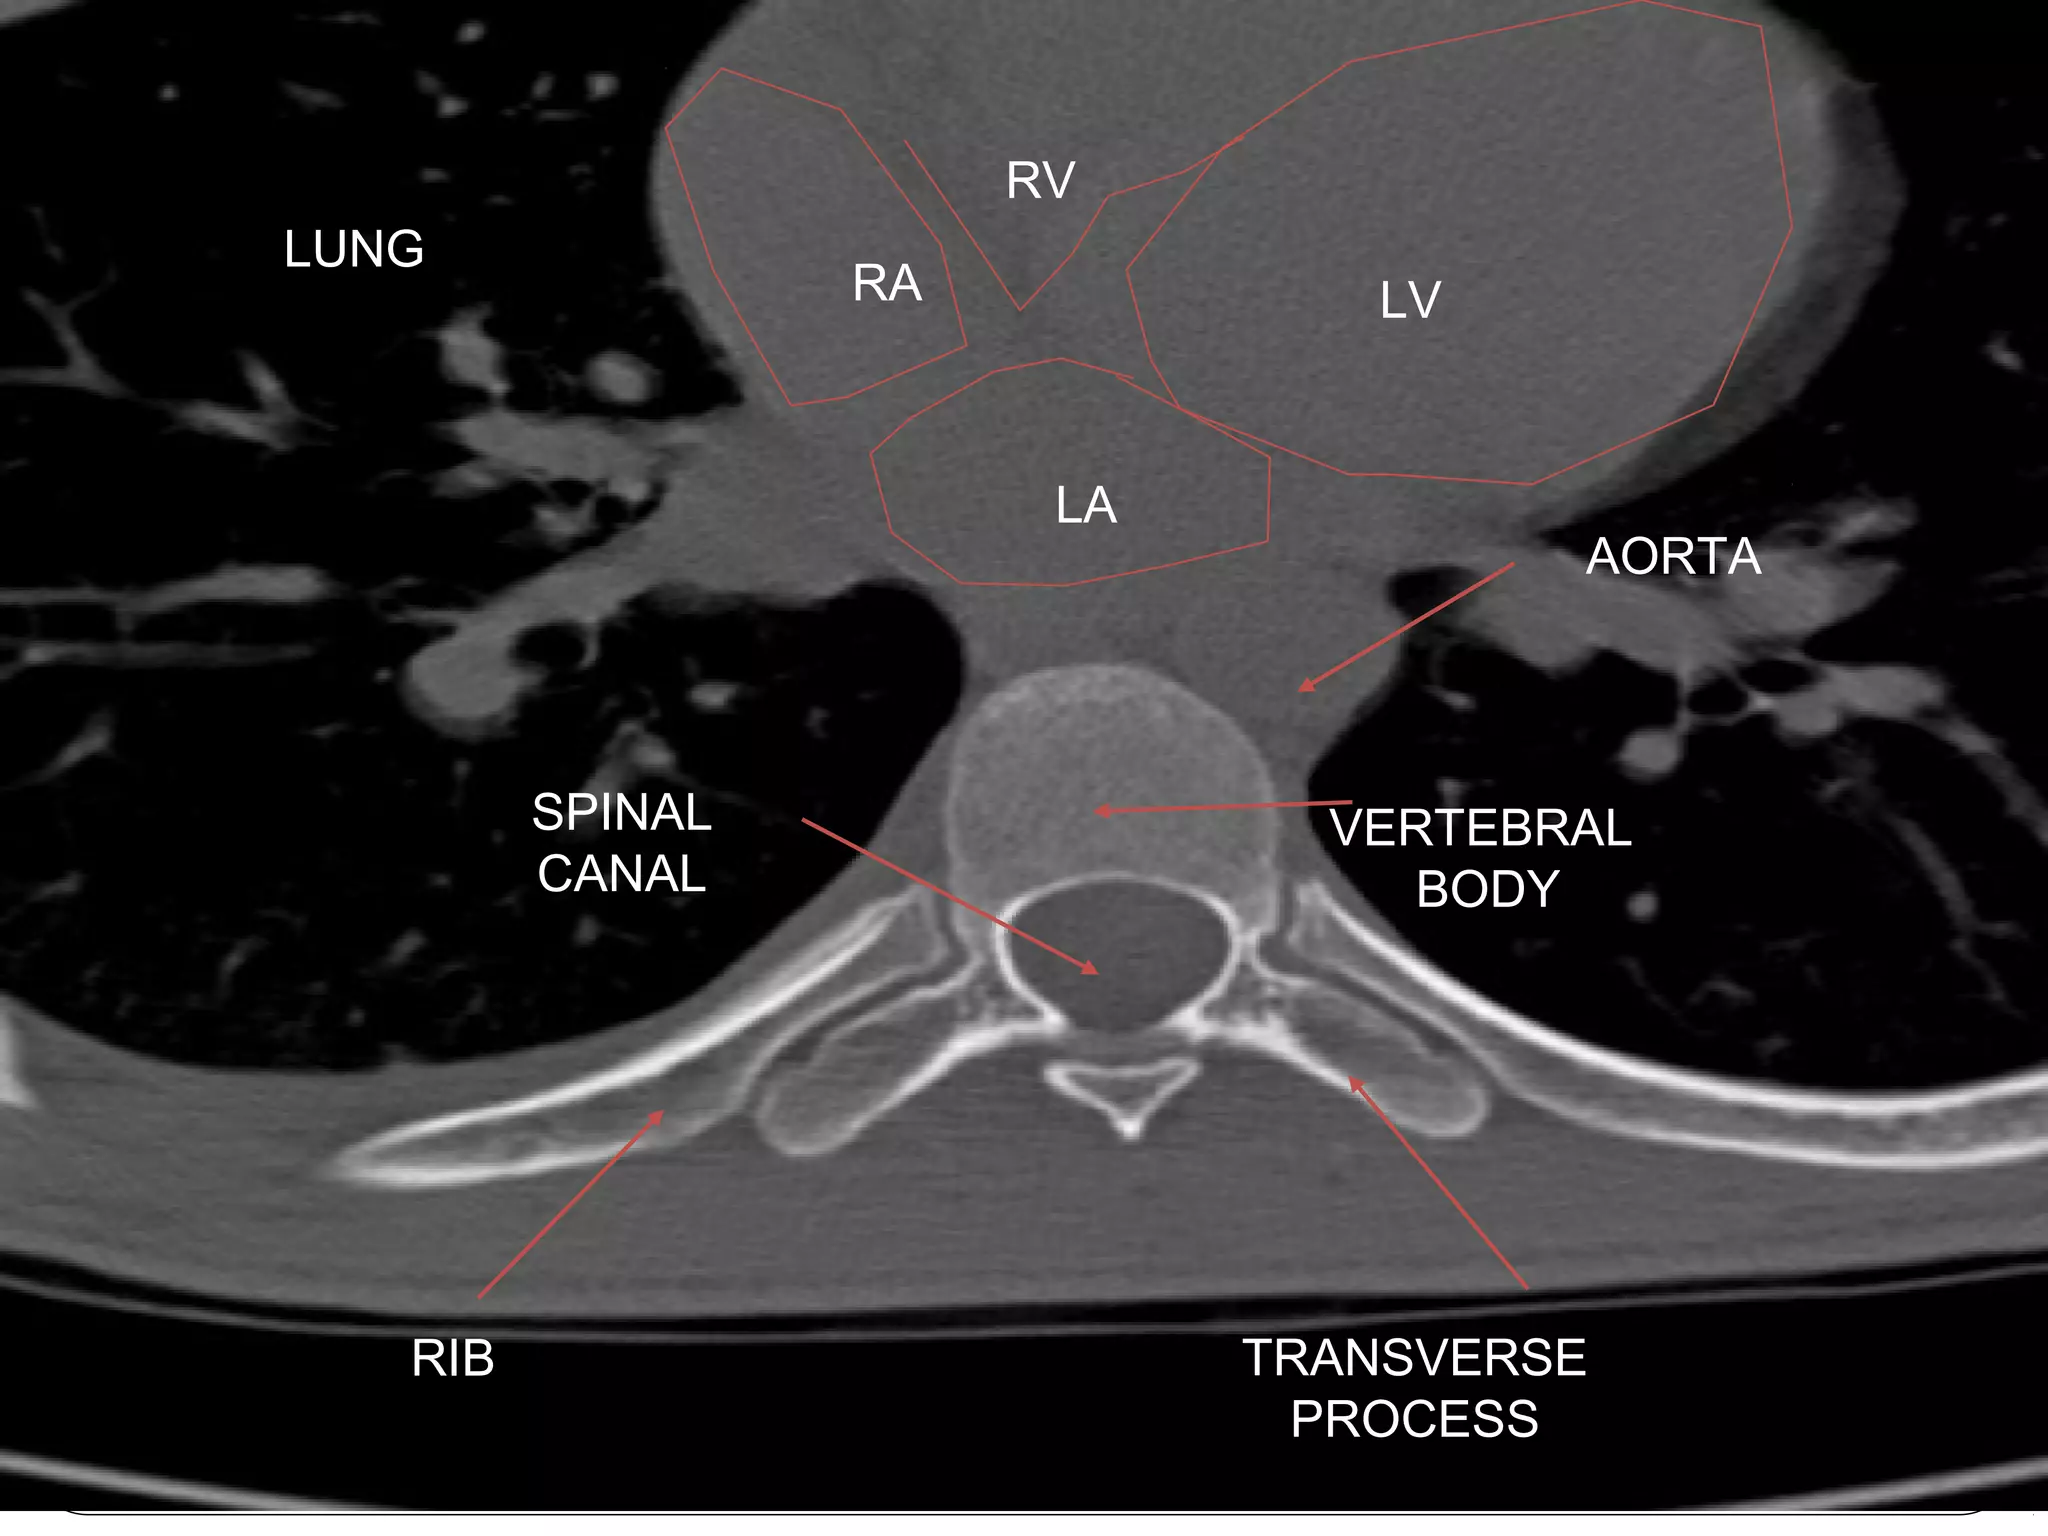

Computed Tomography (CT)

LV

VERTEBRAL

BODY

SPINAL

CANAL

TRANSVERSE

PROCESS

RIB

LUNG

RA

LA

RV

AORTA